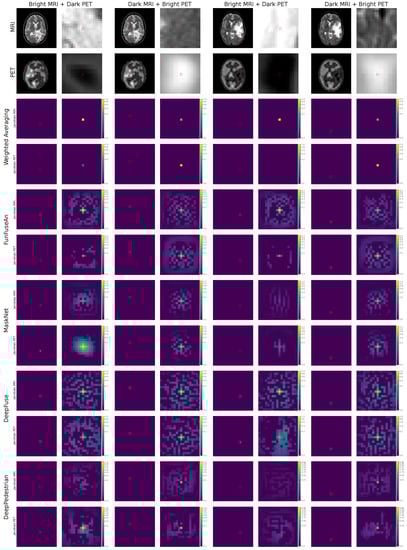

6.3. Jacobian Images

The jacobian images of the selected principle pixel is shown in Figure 7. The analysis of the jacobian images will help in understanding the influence of the neighborhood pixels located around the principle pixel in the clinically relevant regions of the input image. It will also assist in visually comparing the neighborhood influence of MRI pixels with PET pixels.

6.3.1. Weighted Averaging

The jacobian MRI and jacobian PET images within the region with bright MRI and dark PET intensities for both the test examples show a higher gradient of the principle pixel in the jacobian MRI image compared to the jacobian PET image. For the dark MRI and bright PET intensities, there is a relatively high gradient in the principle pixel of the jacobian PET image showcasing sensitivity to changes in the bright PET pixel. One crucial observation from each of the jacobian images is that there is no influence of the neighborhood pixels on the prediction of the fused principle pixel since Weighted Averaging performs the per-pixel computation of fused pixel intensities.

6.3.2. FunFuseAn

After analyzing the jacobian MRI and jacobian PET images within the region of bright MRI and dark PET intensities, it can be observed that similar to the Weighted Averaging method, there is a higher gradient value for the principle pixel of the jacobian MRI image. The immediate neighborhood pixels in the jacobian MRI image also have significant gradient values meaning these pixels also influence the outcome of fused principle pixel. This is clinically useful since the change in intensities of pixels located within the necrotic core should affect the fused principle pixel. Additionally, there are more positive gradient values for the outer neighborhood pixels in the jacobian MRI image than the jacobian PET image. For the combination of dark MRI and bright PET intensities, however, there are low gradients for the principle pixel in both jacobian MRI and jacobian PET images. This conveys that the fused principle pixel is relatively stable to small changes in the bright PET and dark MRI pixel intensities. Hence, visualizing principle pixel in the jacobian images does not give much information about which input principle pixel has a higher influence on the fused principle pixel. On the other hand, the neighborhood pixel influence on the fused principle pixel is quite widespread due to the large number of positive gradients in both the jacobian MRI and jacobian PET images.

6.3.3. MaskNet

For the combination of bright MRI and dark PET intensities, the jacobian images in the first test example convey quite distinct characteristics compared to the jacobian images in the second test example. For the first test example, the jacobian PET image has a much higher gradient for the principle pixel compared to the jacobian MRI image. This reveals a high sensitivity of the fused principle pixel within the necrotic tumor core with respect to small changes in the pixel intensity of the PET principle pixel whereas the fused principle pixel is quite stable to changes in the MRI principle pixel. Additionally, the influence of neighborhood pixels of PET within the dark necrotic tumor core on the fused principle pixel is highly intense compared to neighborhood pixels of MRI. This conveys that the changes in the pixel intensities of the PET inside the dark necrotic core can greatly affect the fused principle pixel while the PET pixels outside the necrotic core boundary have a negligible effect on the fused principle pixel. However, in the second test example, both the jacobian MRI and jacobian PET images have low gradients for the principle pixel as well as in the neighborhood region within the necrotic core. This demonstrates that the network requires quite significant changes in these features to change the fusion output. For the combination of dark MRI and high PET intensities in both the test examples, the jacobian MRI and jacobian PET have similar properties to FunFuseAn where there are low gradients for the principle pixel in both the images; therefore, equally influencing the fused principle pixel. However, there are fewer neighborhood pixels in the jacobian MRI and jacobian PET images that influences the principle pixel when compared to the FunFuseAn network.

6.3.4. DeepFuse

The jacobian images in both the test examples, when visualized in the regions of bright MRI and dark PET intensities show a significantly high number of neighborhood pixels influencing the fused principle pixel while a high gradient value for the principle pixel can be seen in the jacobian MRI image compared to the jacobian PET image. Therefore, the fused principle pixel is highly sensitive to changes in the MRI pixel while it is stable to changes in the PET pixel. By analyzing the jacobian images for the combination of dark MRI and bright PET intensities, it is observable that the gradient values at the principle pixel are low; therefore, showcasing stability to the pixel intensity changes from both the modalities while widespread neighborhood pixels are influencing the fused principle pixel.

6.3.5. DeepPedestrian

The combination of bright MRI and dark PET intensities in the first test example shows different jacobian results compared to the second test example. It can be noticed that the gradient value of the principle pixel in the jacobian MRI image is low while the gradient for the principle pixel is high in the jacobian PET image. This suggests that the fusion network is very stable to changes in the MRI pixel while sensitive to changes in the PET pixel within the necrotic tumor core. There are also positive gradients for the neighborhood pixels within the clinically important necrotic sub-region of glioma in the jacobian PET images due to which these pixels also influence the fusion principle pixel prediction. In the jacobian PET image, there is some influence from the neighborhood pixels outside the necrotic tumor core, but they have low gradients compared to the gradients of the neighborhood pixels within the necrotic core. The jacobian images for the bright MRI and dark PET intensities in the second test example have unique characteristics since both the jacobian MRI and jacobian PET images have very low gradients for the principle pixel as well as for the neighborhood pixels. Therefore, the network is very stable to changes in pixel intensities in this specific region of interest. For the combination of dark MRI and bright PET intensities, both the test examples show similar results where the neighborhood pixel influence on the fused principle pixel are relatively low in both the input modalities while the gradients for the principle pixel are also low meaning that the network does not get influenced by changes in pixels of each of the input modalities.

6.3.6. Summary

The analysis of jacobian images helped to visually compare the influence of the input neighborhood pixels from each of the input modalities on the fused principle pixel. It was observed that most of the fusion-based neural networks have a significant influence on neighborhood pixels. This visual analysis was not possible by only interpreting the guidance and fused images due to which jacobian images provide additional interpretation towards the suitability of a particular fusion method in a clinical setup. It was observed that Weighted Averaging has no neighborhood influence which is understandable by the fact that it is a per-pixel computation scheme. The MaskNet network, however, provides clinically favorable results as it has a high influence of neighborhood pixels within the necrotic core and very low influence from the pixels outside the necrotic core boundary.